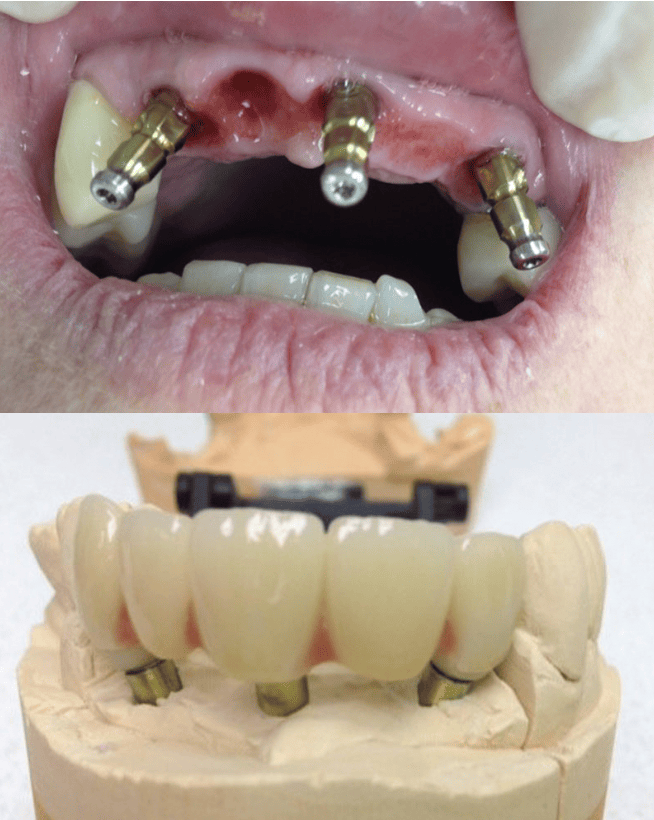

4. Phase prothétique

Une fois l’ostéointégration réussie, le pilier prothétique est fixé, puis la prothèse (couronne, bridge ou dent artificielle) est conçue et posée sur mesure.

L’empreinte, la couleur, la forme sont personnalisées pour un rendu esthétique naturel.